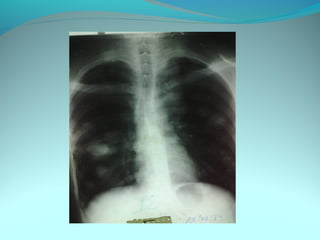

Image radiologique bilaterale

A droite : clarté sous claviculaire et axilaire droite arrondie de 3 cm de

diam entourée d une paroi de 4mm d’épaisseur

Le 1/3 sup du poumon droit est le siege d’opacité nodulaire avec

quelque clarté

A gauche: le 1/3 moyen est le siege d’opacité nodulaire et de clarté de

taille variable

DIAGNOSTIC:

Tuberculose pulmonaire bilaterale cavitaire